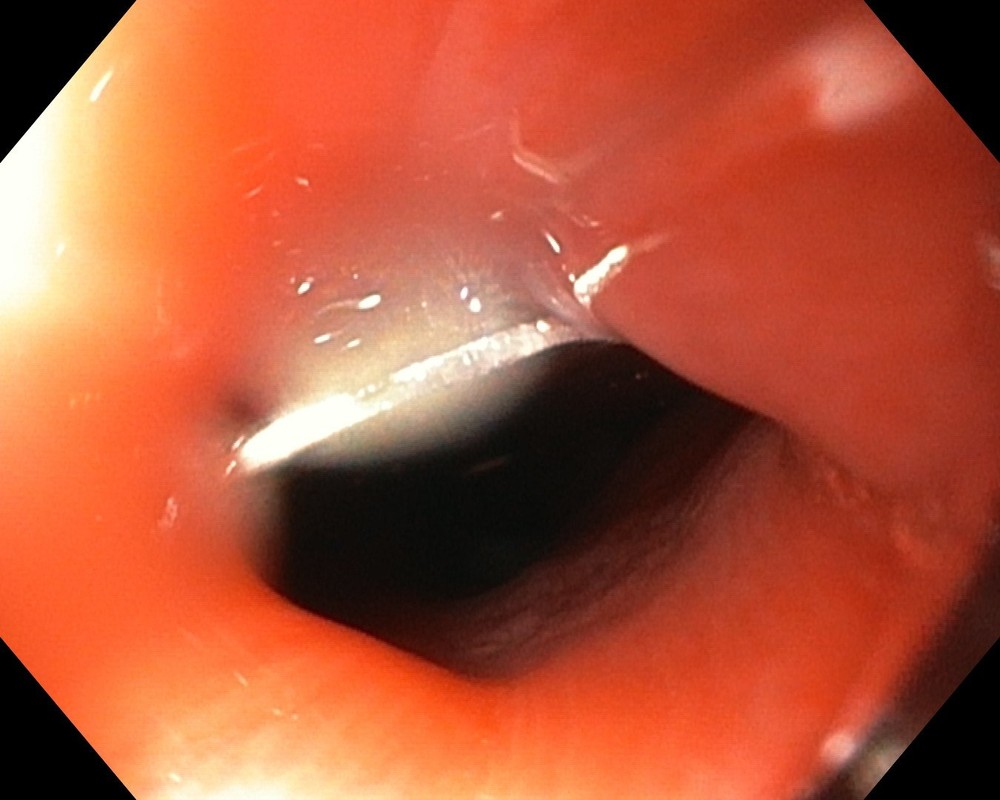

Bệnh nhi nhanh chóng được chuyển lên Bệnh viện Nhi Đồng 1 với chẩn đoán hóc dị vật. Qua kiểm tra, bác sĩ phát hiện, dị vật có hình con cá với nhiều cạnh sắc nhọn đang nằm trong thực quản bệnh nhi. Sau hội chẩn, bệnh nhi đã được bác sĩ chỉ định nội soi lấy dị vật.

Hình ảnh con cá đồ chơi bị kẹt lại trong thực quản khiến bệnh nhi không thể ăn uống được

BS Hoàng Vinh cho biết, trong quá trình nội soi, hình ảnh trên camera cho thấy dị vật là con cá nhựa dài khoảng 2cm, có nguy cơ gây tổn thương thực quản của trẻ. Ê kíp nội soi đã gắp thành công dị vật ra ngoài. Bệnh nhi may mắn khi không bị tổn thương thực quản. Sau khi lấy được dị vật, sức khỏe của trẻ đang bình phục tốt.